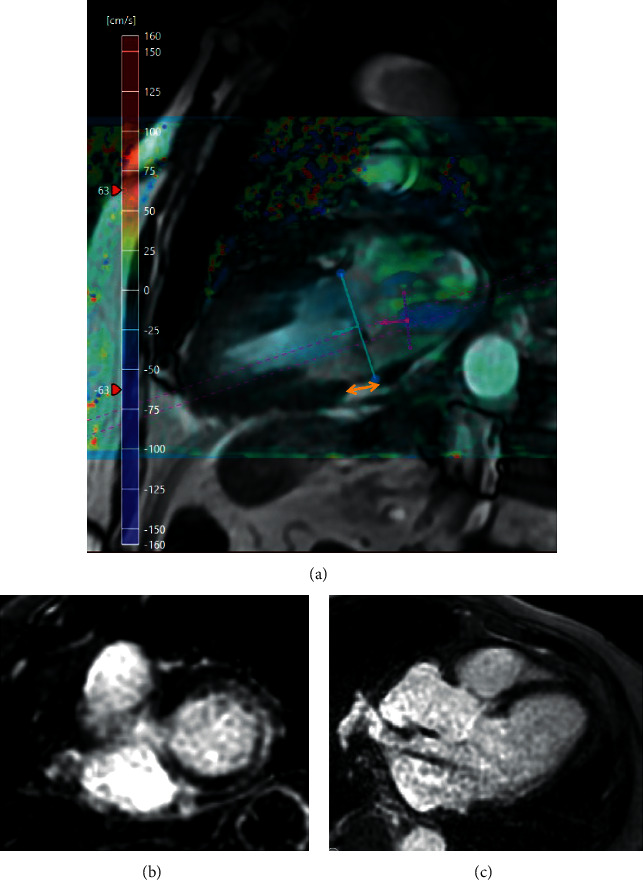

心血管磁共振成像(CMR)对了解各种疾病的过程和病理生理机制产生了巨大影响。最近,它对瓣膜性心脏病患者的诊断和风险分层做出了重大贡献。随着 CMR 的应用越来越广泛,它可以对左心室容积和质量进行详细、可重复、定性和定量的评估,从而评估瓣膜病变对心肌的血流动力学影响。利用特征跟踪 CMR 方法对常规获取的图像进行后处理,可获得有关心肌变形和应变参数的宝贵信息,这些信息表明存在亚临床心室损伤,而射血分数(EF)等传统测量方法仍无法检测到这些损伤。由于越来越多的证据表明纤维化的存在与不良事件和预后有关,因此 T1 图谱和晚期钆增强 (LGE) 成像可提供深层心肌组织特征,从而改变了对患者进行风险分层的方法。本综述总结了目前有关 CMR 在主动脉瓣狭窄或二尖瓣反流患者左心室评估中的作用及其在诊断、风险分层和管理中的价值的证据。

Cardiovascular magnetic resonance (CMR) imaging has had a vast impact on the understanding of a wide range of disease processes and pathophysiological mechanisms. More recently, it has contributed significantly to the diagnosis and risk stratification of patients with valvular heart disease. With its increasing use, CMR allows for a detailed, reproducible, qualitative, and quantitative evaluation of left ventricular volumes and mass, thereby enabling assessment of the haemodynamic impact of a valvular lesion upon the myocardium. Postprocessing of the routinely acquired images with feature tracking CMR methodology can give invaluable information about myocardial deformation and strain parameters that suggest subclinical ventricular impairment that remains undetected by conventional measures such as the ejection fraction (EF). T1 mapping and late gadolinium enhancement (LGE) imaging provide deep myocardial tissue characterisation that is changing the approach towards risk stratification of patients as an increasing body of evidence suggests that the presence of fibrosis is related to adverse events and prognosis. This review summarises the current evidence regarding the utility of CMR in the left ventricular assessment of patients with aortic stenosis or mitral regurgitation and its value in diagnosis, risk stratification, and management.